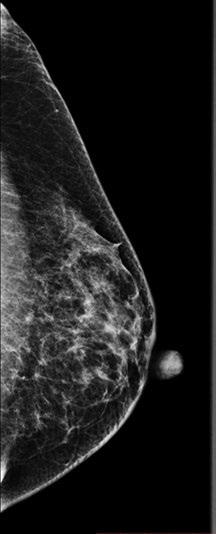

Te hemos hablado de mamografía, pero te preguntarás: ¿qué es? La mamografía es una técnica radiológica especializada que utiliza rayos X para obtener imágenes precisas del tejido mamario. Se emplea principalmente para el tamizaje y diagnóstico del cáncer de mama.

Durante este examen, la paciente se coloca frente a un aparato de rayos X de baja dosis, diseñado especialmente para comprimir las mamas entre dos placas. Esta comprensión ayuda a extender el tejido mamario, lo que garantiza la obtención de una imagen nítida de las estructuras internas de la mama.

En este contexto, la mamografía de tamizaje es una herramienta esencial para la detección temprana en mujeres asintomáticas y el radiólogo es el encargado de su interpretación. Además de esta técnica de imagen, se realizan otros estudios, como ecografías mamarias, resonancias magnéticas y biopsias guiadas por imagen. Estos estudios complementan la información proporcionada por las mamografías, al ofrecer detalles adicionales sobre las características de las lesiones en caso de obtener un resultado positivo.

La densidad mamaria se refiere a la cantidad de tejido glandular* presente en las mamas de una mujer. Cuando un seno tiene una mayor proporción de tejido glandular en comparación con el tejido graso*, se considera que tiene una densidad mamaria alta.

Esto no es una condición patológica ni significa que se tenga una enfermedad en la mama. Simplemente, indica que el examen requiere un estudio adicional, como un ultrasonido, para realizar una exploración más completa.